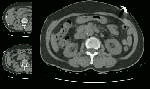

The elderly female shown in the case below presented with right flank pain. A non-contrast CT scan of the abdomen was performed which demonstrated displaced intimal calcification (arrow on coned view) within the abdominal aorta.

Non-contrast CT: